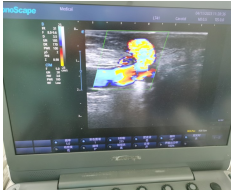

2023年4月11日,州医院血液净化室收治了1位52岁女性透析患者,该患者内瘘属于高位内瘘,血管短且迂曲,为了减轻患者的穿刺痛苦,护士长王维慧与超声科兰晓蓉主任协作成功完成了首例超声引导下内瘘穿刺术,该技术目前在省内属于较为先进的技术。

超声引导下的动静脉瘘穿刺术,能够清晰地明确动静脉内瘘口位置、血管走行、血管深度、血管长度等信息,超声引导下穿刺时可以实时显示穿刺路径针尖进针位置,使血管穿刺可以做到精准定位,大大提高一次性穿刺成功率,减轻患者穿刺中的痛苦及对穿刺血管的反复损伤,尤其适用内瘘首次使用、血管迂曲、距皮深度较大的患者。